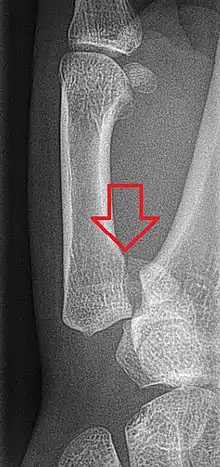

| Bennett fracture on x-ray | |

Bennett fracture is a type of partial broken finger involving the base of the thumb, and extends into the carpometacarpal (CMC) joint.[1]

This intra-articular fracture is the most common type of fracture of the thumb, and is nearly always accompanied by some degree of subluxation or frank dislocation of the carpometacarpal joint.

In the case of the Bennett fracture, the proximal metacarpal fragment remains attached to the anterior oblique ligament, which in turn is attached to the tubercle of the trapezium bone of the CMC joint. This ligamentous attachment ensures that the proximal fragment remains in its correct anatomical position.

The distal fragment of the first metacarpal bone possesses the majority of the articular surface of the first CMC joint. Unlike the proximal fracture fragment, strong ligaments and muscle tendons of the hand tend to pull this fragment out of its correct anatomical position.

Though these fractures commonly appear quite subtle or even inconsequential on radiographs, they can result in severe long-term dysfunction of the hand if left untreated. In his original description of this type of fracture in 1882, Bennett stressed the need for early diagnosis and treatment in order to prevent loss of function of the thumb CMC joint, which is critical to the overall function of the hand.[4]